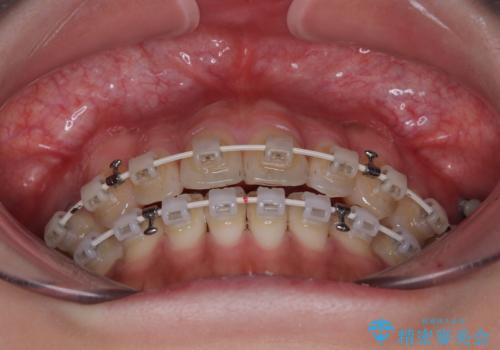

開咬をワイヤー装置で矯正治療

- 矯正装置

- 審美装置

- 10ヶ月

治療開始から8ヶ月ほどで遠方への転勤が決まりましたが、歯列は概ね整っていたため、その後は東京出張を狙って治療を終える処置を行うことができました。